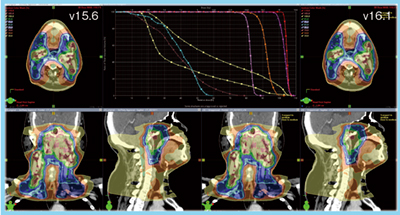

一方,シングルアイソセンタのRapidArcは,最適化パラメータの設定を手動で行うため,計画者の経験に依存する。しかし,放射線治療計画装置「Eclipse」のv13.5からknowledgeベースプランニング「RapidPlan」が搭載されたことで,特に頭頸部がんや膵がん,直腸がんなどでは経験に依存しない治療計画の作成が可能となり,作成に要する時間も大幅に削減された。また,Eclipse v15.5では,最適化を支援する「Multi Criteria Optimization」などの機能が追加されたほか,GPUによる線量計算の高速化,RapidPlanの機能強化などが図られた。さらに,Eclipse v16.1では,GPUを用いてRapidArcの最適化計算が可能となったことで,スループットが格段に向上している。図2はバージョンアップ前後の線量分布の比較であるが,線量体積ヒストグラム(DVH)や線量分布もほぼ一致している。

図2 Eclipse v15.6とv16.1の線量分布の比較